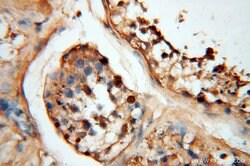

| Immunohistochemistry (Paraffin) | |

| Human, Mouse, Rat | |